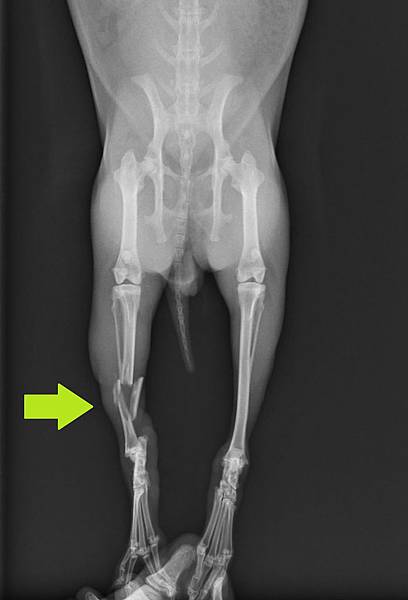

本病例為一隻年約2歲的兔子,主人發現時後肢已經無法負重,經兔友介紹後送至本院

拍攝X光後確認骨折部位為右後肢脛骨骨幹粉碎性骨折

70_203_20120329215626.0就診時脛骨側照

70_204_20120329215857.0 就診時脛骨正照